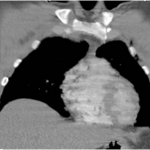

A 15-year-old male presented to the clinic with his mother for evaluation of a right IC avulsion that occurred 1 week prior. The patient initially presented to the emergency department and was diagnosed with a single AP hip/pelvis bilateral radiograph (Fig. 1). The AP pelvic view demonstrated an acute 2–3 mm displaced avulsion fracture of the right anterior IC. The patient was at football practice when a teammate’s helmet collided with his right pelvic area. He felt an immediate “pop” and felt pain. The emergency department recommended pediatric orthopedic follow-up, gave him crutches, and instructed him not to bear weight. The patient endorsed pain in his right hip area for a few days after the injury that had since subsided and intermittent numbness in his right anterolateral thigh. The patient’s examination resulted in mild point tenderness over the fracture site and an antalgic gait. There was also numbness on palpation on the anterolateral thigh, consistent with LFCN distribution. There was no obvious deformity, normal range of motion of lower extremities without pain, and no pain with abdominal or oblique crunches. No further radiologic studies were obtained this visit. The patient and his mother were instructed to bear weight as tolerated, avoid high-impact activities, use crutches as needed, and return to the clinic in 4–6 weeks for a repeat examination and AP hip/pelvis radiograph. At the 1-month follow-up, the patient reported no pain or numbness. His examination was normal, with resolution point tenderness and numbness. There was also no pain with crunches. The AP hip/pelvis radiograph showed a healing avulsion fracture of the right anterior IC (Fig. 2). The patient was told to resume all activities as tolerated with no plan to follow up unless needed.